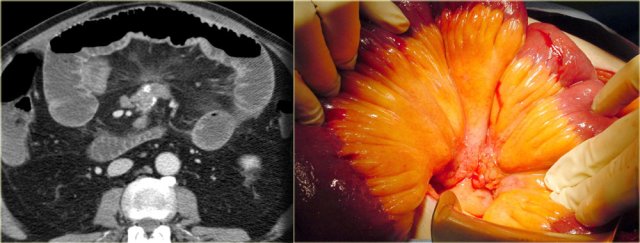

Mesenteric cyst - Lymphangioma

Mesenteric cyst is a descriptive term for any cystic lesion within the mesentery.

Usually it is a lymphangioma.

Other mesenteric cysts like enteric duplication cyst, enteric cyst, nonpancreatic pseudocyst and mesothelial cyst are very uncommon and have no specific features.

Lymphangioma is a benign lesion of vascular origin.

Most lymphangiomas are located in the neck, but 5% of lymphangiomas are abdominal.

Lymphangioma has enhancing septa.

Unlike in cystic peritoneal metastases, ascites is not a feature of lymphangioma.

When you see a septated cystic lesion without ascites the most likely diagnosis is a lymphangioma.

Lymphangioma is often closely associated with the small bowel.

At surgery it is usually very difficult to separate the tumor from the bowel and in many cases the bowel also has to be resected.

The case on the left is also a lymphangioma.

Notice that CT does not always appreciate the septations, although the specimen clearly shows multiple septations.

Ultrasound or MR depict these septations better than CT.